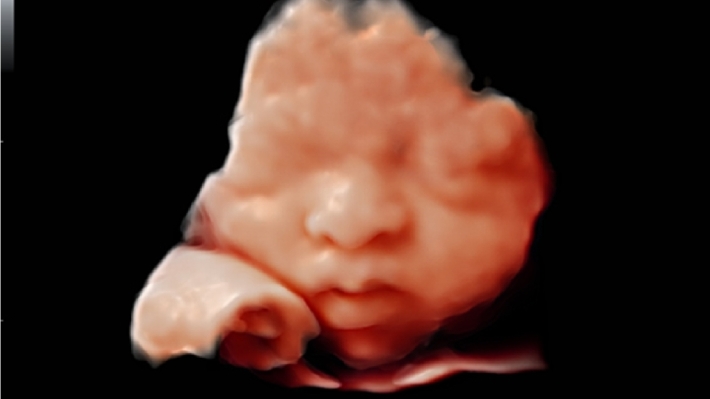

УЗИ-аппарат Mindray DC-70 — это современная ультразвуковая система экспертного класса, предназначенная для проведения диагностических исследований в различных областях медицины, включая кардиологию, акушерство и гинекологию, абдоминальные и сосудистые исследования. Аппарат сочетает высокое качество изображения с широким набором функциональных возможностей, что делает его эффективным инструментом для диагностики.

• Многофункциональность: Поддержка различных режимов сканирования, включая 2D, 3D/4D, цветное допплеровское картирование и другие, позволяет использовать аппарат для широкого спектра медицинских задач;

• Smart OB™ — программа автоматического расчета основных акушерских показателей;

• Smart NT — программа для автоматического определения и расчета толщины воротникового пространства у плода;

• iLive™ — технология 3D/4D-визуализации с функцией постобработки изображений;

Изображения